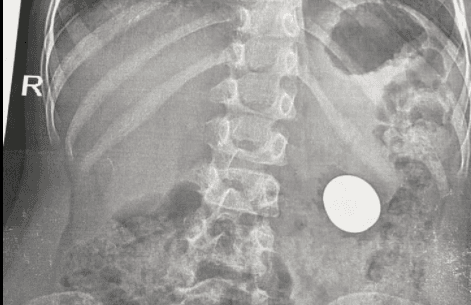

До Львівської обласної дитячої лікарні «Охматдит» потрапила семирічна дівчинка, яка проковтнула п’ять магнітиків. Вдома дитина починала задихатися, її турбував дискомфорт у шиї – батьки викликали швидку допомогу. Про це повідомили на сторінці лікарні.

«Коли дитину привезли в лікарню, їй невідкладно зробили рентген і, аби не допустити потрапляння магнітів у кишківник, що могло викликати перфорацію його стінок, хірурги одразу ж за допомогою сучасного інструментарію під контролем оптики, дістали магніти із стравоходу», – йдеться в повідомленні.

Медики нагадують дорослим про магнітну небезпеку для малечі. Магніти мають надзвичайну силу притягання, тож пошкоджують внутрішні органи дитини, трапляється, подекуди вони пробивають їх і утворюють справжні дірки. Уже за кілька годин магнітики можуть стати причиною некрозу кишки.